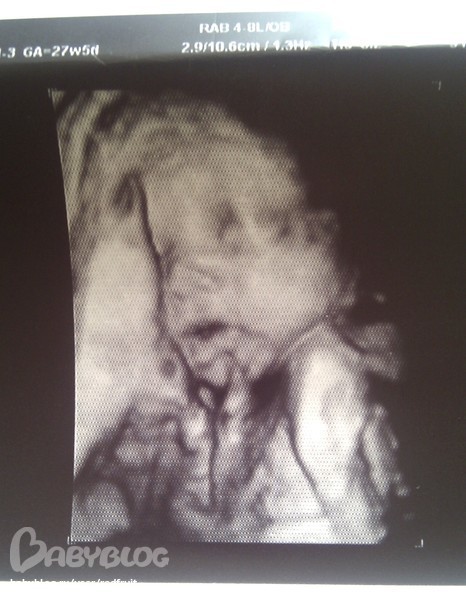

А последние фотки малыша такие, 27 недель и 5 дней:

приставучая пуповина все время мешалась около рта )))